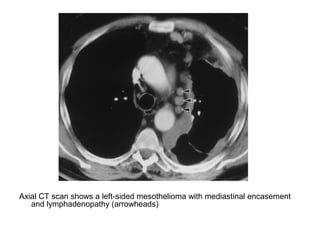

Axial CT scan shows a left-sided mesothelioma with mediastinal encasement

and lymphadenopathy (arrowheads)